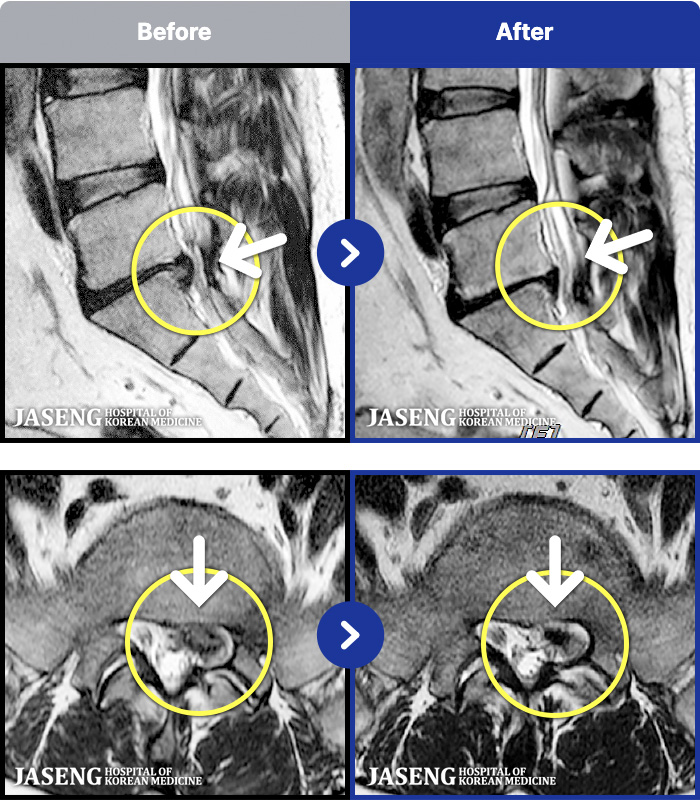

MRI ġ

1,301 MRI ũ ʸ Ȯϼ.